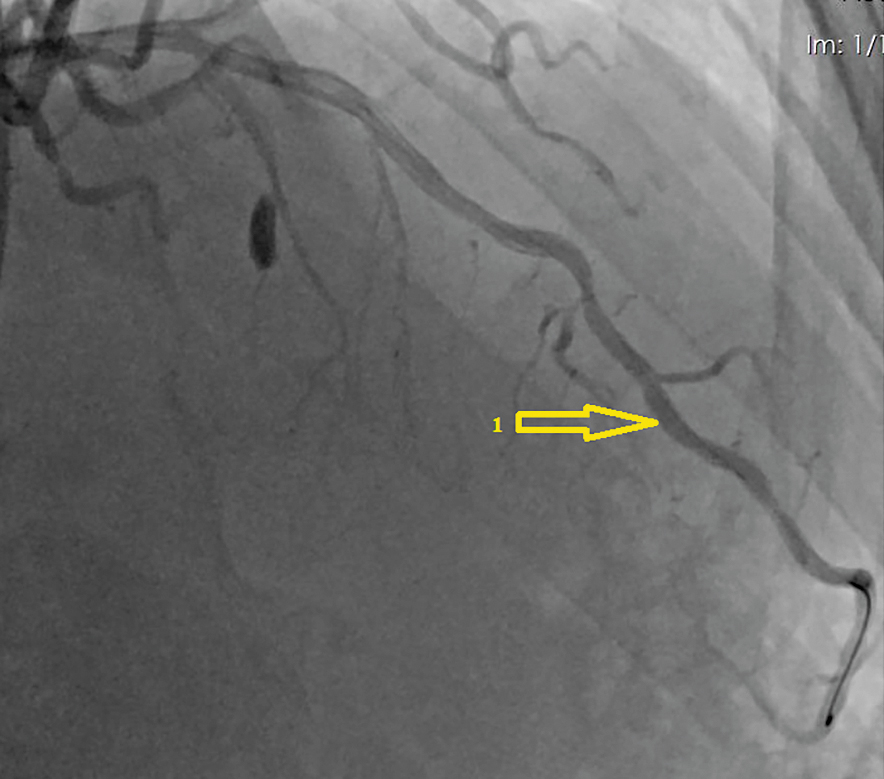

В 2020 г. пациент обратился к кардиологу с жалобами на боли в области сердца при физической нагрузке. По данным скринингового цветного дуплексного сканирования брахиоцефальных артерий и дальнейшей их ангиографии визуализирован 80% рестеноз ВСА слева (рис. 2), 97% стеноз (субокклюзия) ВСА справа (рис. 3). По результатам коронарографии диагностирован 90% стеноз ПНА (рис. 4).

Рис. 4. Коронарография: 1 — 90% стеноз передней нисходящей артерии. / Fig. 4. Coronary angiography: 1 — 90% stenosis of the left anterior descending artery.